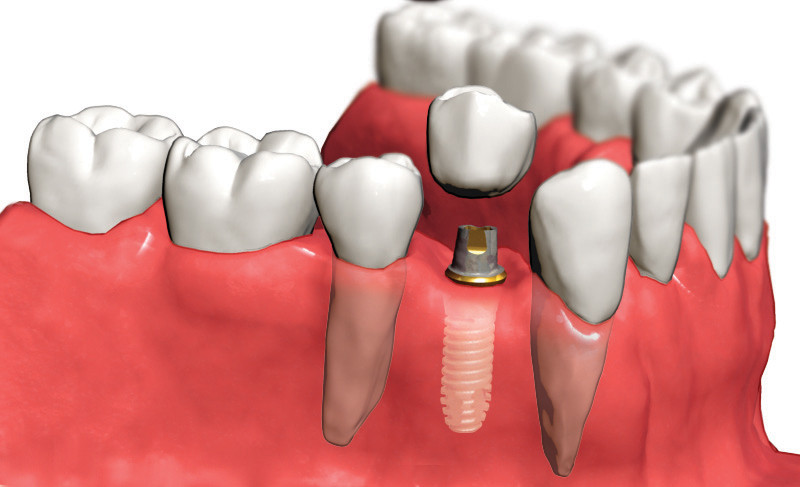

Имплантология Использование зубных имплантатов для возмещения отсутствующих зубов стало настоящим прорывом в стоматологии. Имплантаты способны заместить любое количество отсутствующих зубов. Титановые «шурупы» устанавливаются в челюстную кость и через определенное время становятся опорой для коронок и мостов, которые выглядят, функционируют и ощущаются пациентами как настоящие зубы.

Что такое зубные имплантанты?

• Имплантант является искусственной заменой корня зуба

• Имплантанты устанавливают в кость под десну. Через несколько месяцев имплантант прочно срастается с костью челюсти и может поддерживать искусственную коронку

• Имплантанты можно использовать для замещения одного, нескольких и даже всех зубов

Замещение одного зуба:

• Сначала имплантант устанавливают в кость челюсти. Через некоторое время кость плотно прирастает к поверхности имплантанта.

• После сращения кости имплантантом прикрепляют переходный элемент, который служит опорой для искусственной коронки.

В конечном итоге на опору фиксируют искусственную коронку

Кроме того, имплантаты позволяют избежать обтачивания соседних с дефектом зубов.

Немедленная имплантация — это установка имплантата сразу после удаления зуба. Немедленная имплантация позволяет избежать атрофии костной ткани, сократить сроки протезирования, уменьшить количество посещений хирурга-стоматолога, прием антибиотиков и других препаратов. Немедленное протезирование, т. е. — установка имплантата с одномоментной нагрузкой (изготовлением временной коронки). Такая процедура стала возможна благодаря использованию винтовых титановых имплантатов корневидной формы и новейших костно-замещающих материалов. Имплантация в стоматологии сегодня — это широко распространенный вид лечения, с помощью которого можно решить практически любые проблемы. Варианты протезирования с помощью имплантатов очень разнообразны и удовлетворят любого (даже самого придирчивого) пациента.